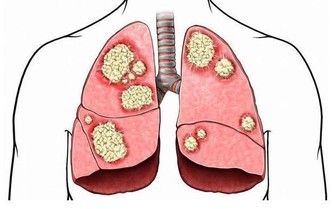

06.肝臟要求少赴宴

肝臟是人體內最大的腺體,主要功能是儲藏、代謝和解毒以及分泌膽汁。

當人們高強度勞動後,肝會進行各種代謝,以補充體內消耗的能源。

對肝威脅最大的是肝炎、肝硬化和肝癌。經常過量飲酒的人群,肝硬化和肝癌的機會比一般人高得多。